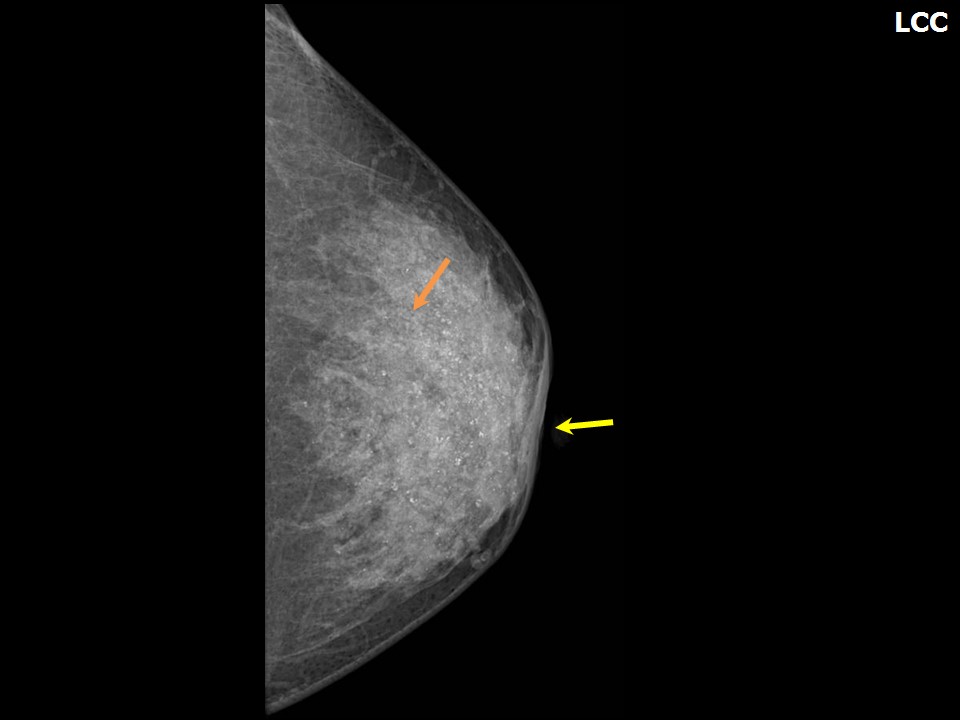

Феномен гипердиагностики в маммографии: примеры и иллюстрации

Раздел: Образы вокруг